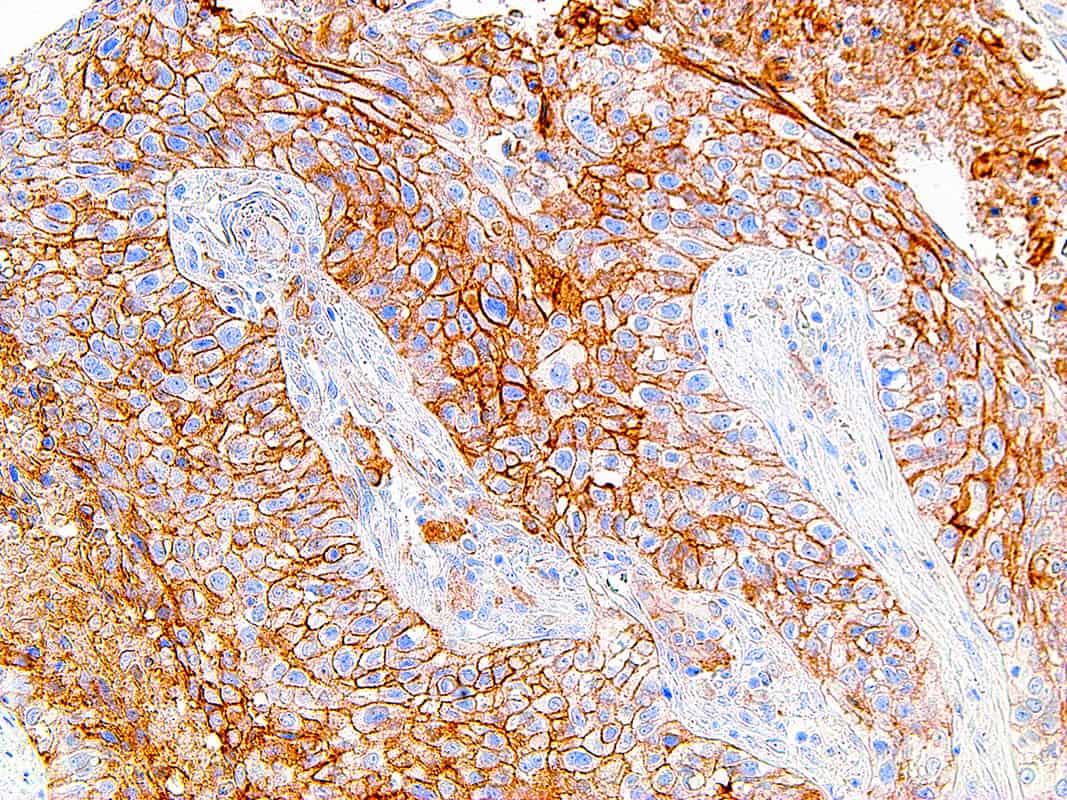

PD-L1

Programmed Death-Ligand 1 (PD-L1), also known as CD274 or B7 Homolog 1 (B7-H1), is a transmembrane protein involved in suppressing the immune system and rendering tumor cells resistant to CD8+ T cell-mediated lysis through binding of the Programmed Death-1 (PD-1) receptor. Overexpression of PD-L1 may allow cancer cells to evade the actions of the host immune system. In renal cell carcinoma, upregulation of PD-L1 has been linked to increased tumor aggressiveness and risk of death, and, in ovarian cancer, higher expression of this protein has lead to significantly poorer prognosis. PD-L1 has also been linked to systemic lupus erythematosus and cutaneous melanoma. When considered in adjunct with CD8+ tumor-infiltrating lymphocyte density, expression levels of PD-L1 may be a useful predictor of multiple cancer types, including stage III non-small cell lung cancer, hormone receptor negative breast cancer, and sentinel lymph node melanoma.

| Positive Control | Tonsil, Lung Adenocarcinoma |